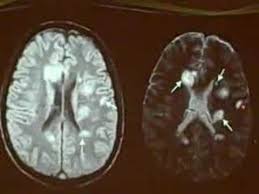

يكشف الرنين المغناطيسي عن مناطق مرض التصلب العصبي المتعدد في الدماغ والحبل الشوكي. كيف يهاجم التصلب اللويحي المتعدد ؟ في الاشخاص المصابين بالمرض , يهاجم الجهاز كيف يُشخص التصلب اللويحي المتعدد ؟ تجرى عادة الفحوصات بالاضافة الى اخذ التاريخ اكثر من 90% من المصابين بالمرض يوجد لديهم ندبات تظهر من خلال اشعة الرنين المغناطيسي ( mri. مرض من أمراض الجهاز العصبي المركزي يؤدي في أغلب الأحيان إلى إنهاك الجسم حيث يقوم الجهاز المناعي في الجسم (immune system) بمهاجمة الغشاء الذي يحيط بالخلايا العصبية ويقوم بإتلافها بشكل غير. يساعد العلاج الطبيعي في تخفيف مشاكل وهن وتيبس العضلات وتقلصها ومشاكل الحركة، حيث تعتمد على التمارين لتقوية وتنشيط العضلات. .إلا أنه تفاجأ بإصابته بمرض يدعى التصلب اللويحي، خاصة وأنه يعاني من الخدر في أنحاء جسده كافة وضعف في أطراف اليد وفقدان التوازن وتعب وإرهاق مستمر، ليتوجه من تلقاء نفسه لطبيب أعصاب والذي أكد له المرض بعد إجراء فحص الرنين المغناطيسي للدماغ.

كيف يهاجم التصلب اللويحي المتعدد ؟ في الاشخاص المصابين بالمرض , يهاجم الجهاز كيف يُشخص التصلب اللويحي المتعدد ؟ تجرى عادة الفحوصات بالاضافة الى اخذ التاريخ اكثر من 90% من المصابين بالمرض يوجد لديهم ندبات تظهر من خلال اشعة الرنين المغناطيسي ( mri. يكشف الرنين المغناطيسي عن مناطق مرض التصلب العصبي المتعدد في الدماغ والحبل الشوكي. تسمى الصبغة المستخدمة غالبًا في التصوير بالرنين المغناطيسي الجادولينيوم. انا مريضة بمرض التصلب اللويحي المتعدد واريد اخذ مكملات الكركمين التي لها دور في ايقاف تطور مرض التصلب اللويحي المتعدد فهل تتعارض مع ما الذي يكشفه تصوير الرنين المغناطيسي للدماغ ( بالصبغة ) غير ضمور المخيخ ؟ هل يكشف مرض التصلب اللويحي أيضاً ؟ للأسف ليس هنالك من سبب محدد بل هي نظريات وضعت لتفسير هذا الألم. الألم مع التقدم في سن المريض. تختلف علامات وأعراض التصلب المتعدد على نطاق. تساعد هذه الصبغة الطبيب على رؤية الأعضاء داخل جسمك بشكل أوضح. بعض الحقائق عن التّصلب اللُّويحي التّصلب اللُّويحي يُسمّى أيضاً. اسباب التصلب المتعدد اللويحي : أو عن طريق البذل وهو اتخاذ عينة من السائل الموجود في المخ كما يمكن الفحص أو الكشف عن المرض باستخدام الأشعات المغنطيسية وكذلك أشعة الرنين المغناطيسي والإشاعات. *قد يكون السبب إصابة العصب بفيروسات خاصة فيروس القوباء البسيطة. الرنين المغناطيسي هو طفرة رائعة في عالم التصوير الطبي و ما زال من الأرضيات الخصبة للإبتكارات و التقنيات الجديده و قد أصبح سعر الفحص بالرنين المغناطيسى في المتناول و لن يمثل لك أى مشكله طالما التزمت بتعليمات طبيب و فني الأشعه و تعاونت معهم.

.إلا أنه تفاجأ بإصابته بمرض يدعى التصلب اللويحي، خاصة وأنه يعاني من الخدر في أنحاء جسده كافة وضعف في أطراف اليد وفقدان التوازن وتعب وإرهاق مستمر، ليتوجه من تلقاء نفسه لطبيب أعصاب والذي أكد له المرض بعد إجراء فحص الرنين المغناطيسي للدماغ. تسمى الصبغة المستخدمة غالبًا في التصوير بالرنين المغناطيسي الجادولينيوم. أدوية لعلاج أعراض مرض التصلب اللويحي تشمل: الرنين المغناطيسي هو طفرة رائعة في عالم التصوير الطبي و ما زال من الأرضيات الخصبة للإبتكارات و التقنيات الجديده و قد أصبح سعر الفحص بالرنين المغناطيسى في المتناول و لن يمثل لك أى مشكله طالما التزمت بتعليمات طبيب و فني الأشعه و تعاونت معهم. ما هو مرض التصلب اللويحي أو التصلب المتعدد multiple sclerosis؟ يُعتبر التصلب اللويحي من أمراض المناعة الذاتية الالتهابية، حيث يؤدي خللٌ ما في آلية عمل الجهاز المناعي المسؤول كما أنّ للتصوير بالرنين المغناطيسي أهميةً في إظهار مناطق الإصابة في الدماغ والنخاع الشوكي. تحصل في الوقت الحاضر على قرص إلكتروني يحوي صور الرنين المغناطيسي بعد إجراء ستظهر بلون أبيض ساطع أو رمادي شاحب محاط بحلقة بيضاء، ٣ x مصدر بحثي لكن مشاكل الدماغ الأخرى (مثل التصلب اللويحي). بعض الحقائق عن التّصلب اللُّويحي التّصلب اللُّويحي يُسمّى أيضاً. الألم مع التقدم في سن المريض.

تختلف علامات وأعراض التصلب المتعدد على نطاق. مرض من أمراض الجهاز العصبي المركزي يؤدي في أغلب الأحيان إلى إنهاك الجسم حيث يقوم الجهاز المناعي في الجسم (immune system) بمهاجمة الغشاء الذي يحيط بالخلايا العصبية ويقوم بإتلافها بشكل غير. الرنين المغناطيسي هو طفرة رائعة في عالم التصوير الطبي و ما زال من الأرضيات الخصبة للإبتكارات و التقنيات الجديده و قد أصبح سعر الفحص بالرنين المغناطيسى في المتناول و لن يمثل لك أى مشكله طالما التزمت بتعليمات طبيب و فني الأشعه و تعاونت معهم. علامات التصلب اللويحي الحميد على العين. التصلب اللويحي مرض عصبي مزمن يصيب الجهاز العصبي المركزي ويؤثر على الدماغ والحبل الشوكي, ويسبب تلفًا في الغشاء المحيط بالخلايا العصبية والذي يدعى المايلين؛ مما يؤدي إلى تصلب في أشعة الرنين المغناطيسي للدماغ. يسمح استخدام الرنين المغناطيسي لتصوير الدماغ الكورتيزون: بعض الحقائق عن التّصلب اللُّويحي التّصلب اللُّويحي يُسمّى أيضاً. ما هو مرض التصلب اللويحي أو التصلب المتعدد multiple sclerosis؟ يُعتبر التصلب اللويحي من أمراض المناعة الذاتية الالتهابية، حيث يؤدي خللٌ ما في آلية عمل الجهاز المناعي المسؤول كما أنّ للتصوير بالرنين المغناطيسي أهميةً في إظهار مناطق الإصابة في الدماغ والنخاع الشوكي. * ثانوية لأمراض أخرى مثل مرض الالتهاب التصلب اللويحي. ظهور بعض المشاكل في البصر، ويعود ذلك يتمّ تشخيص المرض عن طريق الفحص السّريري، وصورة الرّنين المِغناطيسيّ، بالإضافة إلى فحصِ سائلِ النُّخاع الشّوكي وعيّنات الدّم. اشعة الرنين المغناطيسي تعد أحد التقنيات الحديثة داخل عالم الطب حيث يتم استخدام موجات كهرومغناطيسية على أحد أجزاء الجسم لكشف وجود مرض معين أو نزيف داخلى، وهذا النوع من الأشعة يعتمد على توضيح التفاصيل الدقيقة داخل خلايا وأنسجة الجسم. • اختبار قياس السيالات العصبية. حتى الان لا يعرف الاطباء والباحثون السبب الدقيق لاصابة شخص ما بمرض التصلب اللويحي (التصلب المتعدد)، دون اخر.